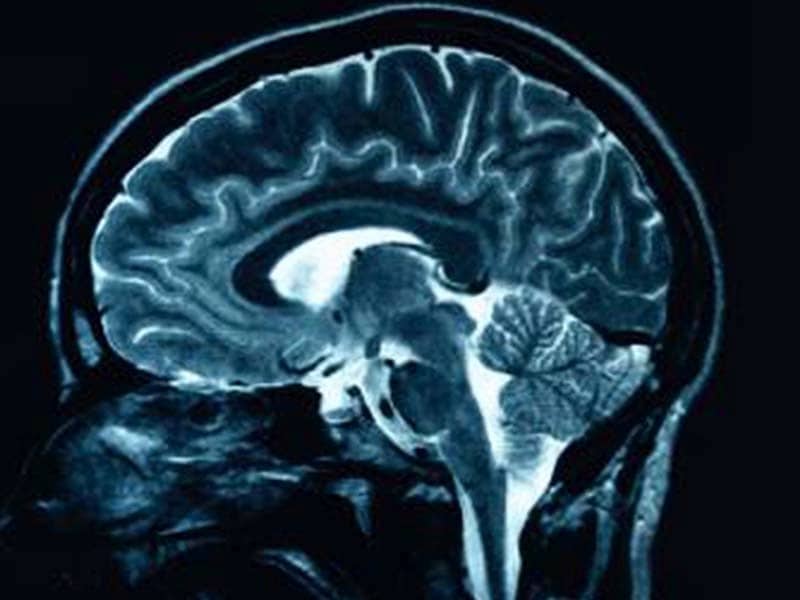

MRI (Magnetic Resonance Imaging) is among the most reliable, elegant, and least invasive tool in medical diagnostics. It has the capability to image structures as complex as the heart and abstract as the mind. Yes, you read it right. It has the ability to capture our thoughts in pixels and voxels. Home-grown Voxelgrids Innovations has done it for us in India.